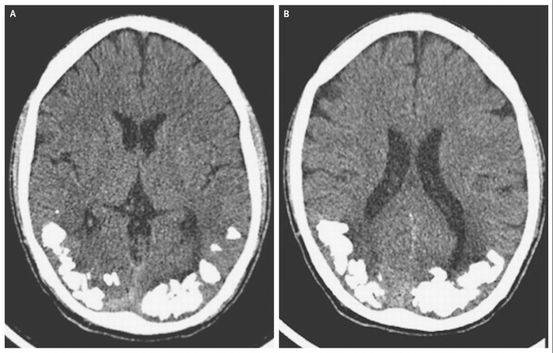

22、脑子里也会长结石啊?

巴西一年轻男子因头痛和视觉问题持续10年而入院。

入院后检查发现他大脑中长了结石样的钙沉积物。据推测这是由于他患有他自己都不知道的胃肠道疾病——乳糜泄而导致。虽然说医生并不能完全解释为什么乳糜泄会导致脑结石,但是猜测可能是乳糜泄使小肠的铁离子吸收功能下降产生的影响。

这个案例发表在2014年的扭英上。